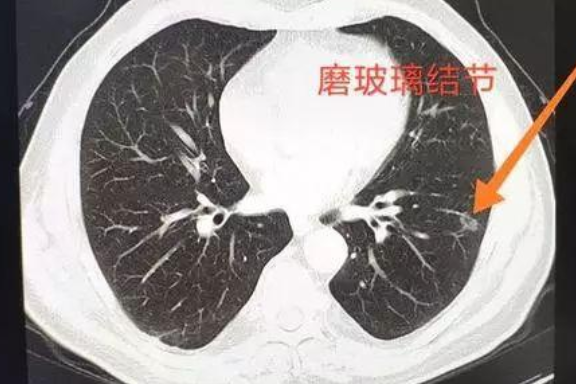

这个肺部的结节有三种,一种是纯磨玻璃结节,就是在薄层ct片上,所出现